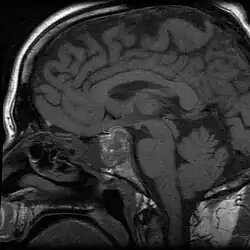

Apoplexy (from Ancient Greek ἀποπληξία (apoplexia) 'a striking away') refers to the rupture of an internal organ and the associated symptoms. Informally or metaphorically, the term apoplexy is associated with being furious, especially as "apoplectic". Historically, it described what is now known as a hemorrhagic stroke, typically involving a ruptured blood vessel in the brain; modern medicine typically specifies the anatomical location of the bleeding, such as cerebral apoplexy, ovarian apoplexy, or pituitary apoplexy.[1][2][3]

From the late 14th to the late 19th century, the diagnosis apoplexy referred to any sudden death that began with abrupt loss of consciousness, especially when the victim died within seconds after losing consciousness. The word apoplexy was sometimes used to refer to the symptom of sudden loss of consciousness immediately preceding death. Strokes, ruptured aortic aneurysms, and even heart attacks were referred to as apoplexy in the past, because before the advent of biomedical science, the ability to differentiate abnormal conditions and diseased states was limited. Although physiology, as a medical field, dates back at least to the time of Hippocrates, until the late 19th century, physicians often had inadequate or inaccurate understandings of many of the human body's normal functions and abnormal presentations. Hence, identifying a specific cause of a symptom or of death often proved difficult or impossible.[4][5][6][7][8]